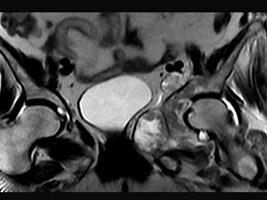

问题 患者 男,38岁,感觉左髋部疼痛,并逐渐加重,体检:左髋部明显肿胀压痛,无明显发热,请选择最佳诊断 ( )

选项 A、软骨肉瘤 B、软骨黏液纤维瘤 C、纤维肉瘤 D、骨肉瘤 E、骨巨细胞瘤

答案 A